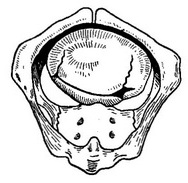

Разгибательное рух. Згадаймо форму і розміри голівки плоду (рис. 52). На малюнку видно, що бипариэтальный розмір головки більше, ніж битемпоральный. Якщо головка вступає у вхід тазу в зігнутому положенні, то її більший поперечний розмір (dist. biparietalis) встановлюється на середині окружності входу, тобто між мисом і лоном, а менший (dist. bitemporalis) - розташований в стороні від прямого розміру.

Отже, при плоскорахітіческій тазі, в якому зменшено саме прямий розмір входу, головка в стані флексії мала б пройти найвужчу частину його своїм великим розміром. При наявному звуження тазу це виявляється неможливим і головка тривалий час залишається рухливою, то згинається або розгинається, в залежності від переймів, до тих пір, поки, нарешті, не встановиться своїм меншим поперечним розміром (битемпоральный) між мисом крижової кістки і лоном. Більший розмір голівки (біпаріетальний) відхилиться в цьому випадку в бік від прямого розміру тазу. Якщо до цього моменту матка буде мати достатній тонус, то таке помірне розгинання голівки зафіксується. При внутрішньому дослідженні породіллі це положення голівки характеризується тим, що великий джерельце буде визначатися на одному рівні з малим або навіть трохи нижче його.

![]() Рис. 52. Початок вставляння голівки при плоскому тазі. Бипариэтальный розмір встановлюється в області істинної кон'югати (вид знизу). |